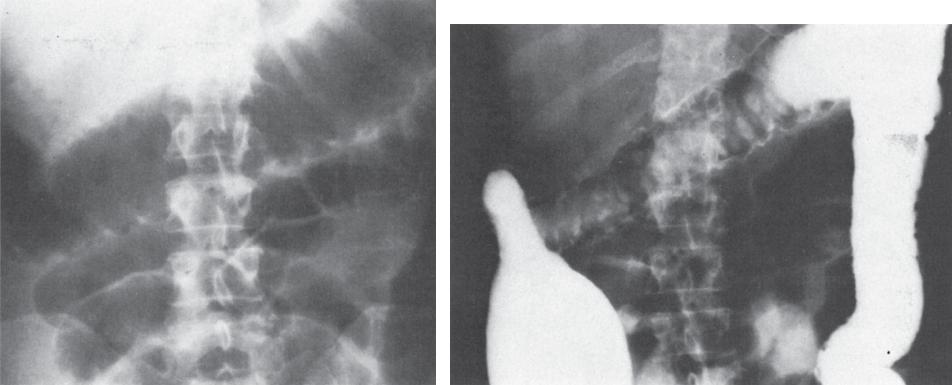

Болезнь Крона:

стриктуры ЖКТ (с кишечной

непроходимостью и без нее),